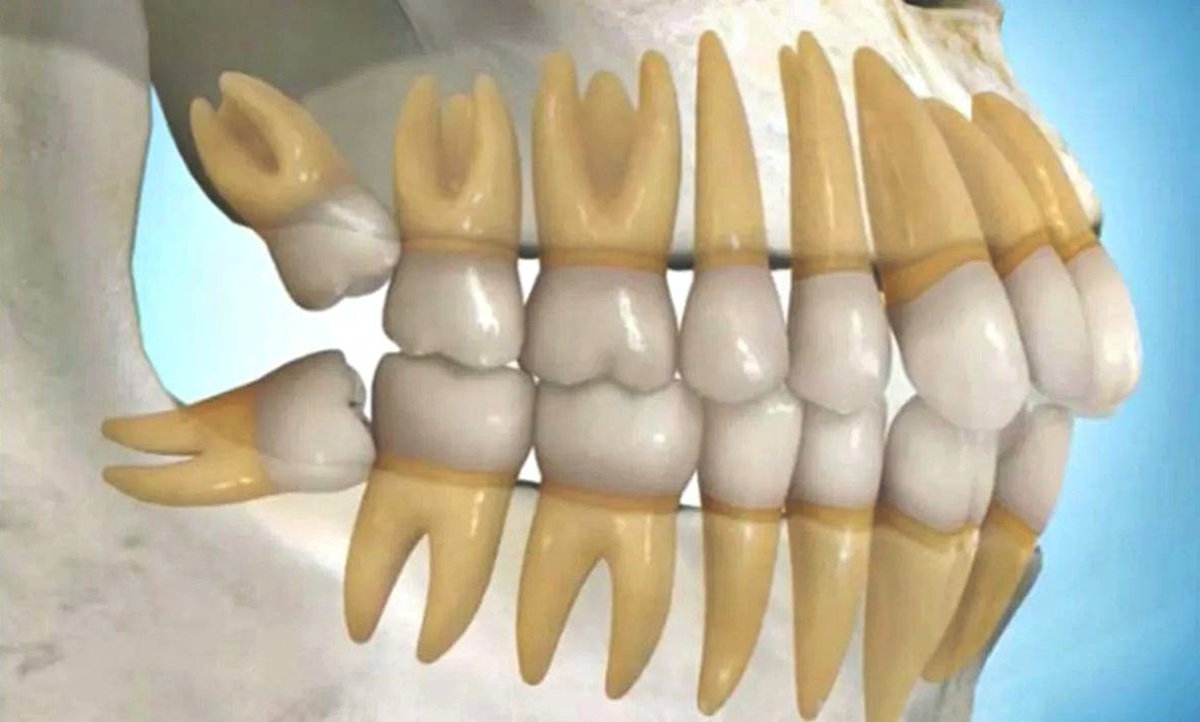

Beynin büyümesi ve gelişimi için çene yapısının küçülmesi, evrimsel süreçte bir zorunluluk haline geldi.

Artık sindirimi kolay etle beslenen atalarımızın, sert otları parçalamak için ihtiyaç duyduğu eski güçlü ve geniş çene yapısı gereksizleşti.

Fazladan diş üretimine harcanan enerji, vücudun başka alanlarına yönlendirilebildi.

Çenenin küçülmesiyle birlikte, en sonda bulunan yirmilik diş için çenede yeterli yer kalmamaya başladı.